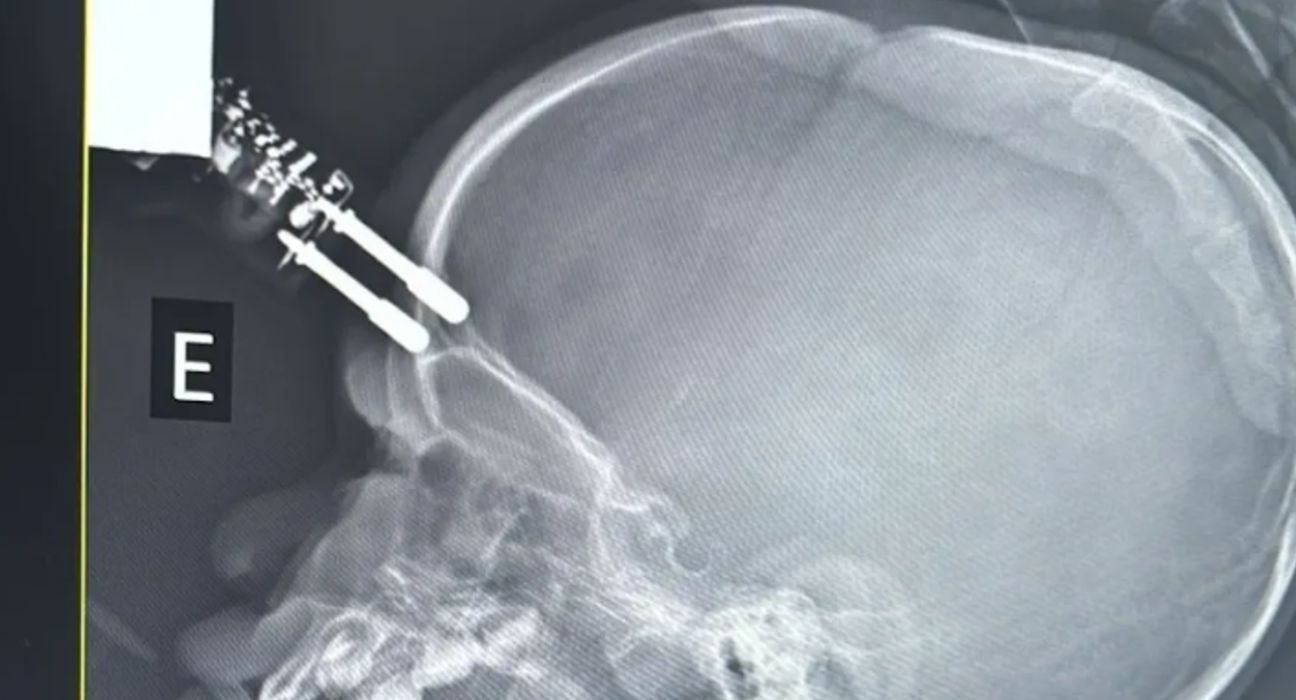

Uma tomografia computadorizada confirmou que o objeto havia atravessado o osso e atingido o tecido cerebral. O médico explicou que o crânio de crianças dessa idade possui apenas alguns milímetros de espessura, o que facilita fraturas e perfurações mesmo em quedas aparentemente simples.

Segundo o neurocirurgião Bruno Castro, responsável pelo atendimento, um dos pinos do carregador havia perfurado o crânio e estava fixado ao osso. Na avaliação inicial, a criança estava consciente, assustada e sem sangramento ativo.

Diante do risco imediato, foi indicada cirurgia de urgência. A paciente foi anestesiada e intubada, e os médicos realizaram a retirada do corpo estranho, lavagem da área atingida, controle de pequeno sangramento e reconstrução da membrana que protege o cérebro.